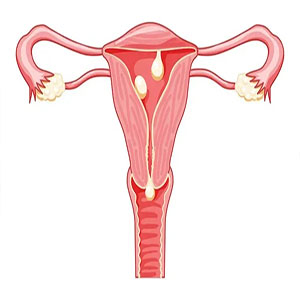

بیماری های زنانگی

بیماری های زنان دستگاه تناسلی زنان در ناحیه لگن قرار گرفته و شامل رحم، تخمدان ها ، لوله…

پولیپ رحمی

عمل هیستروسکوپی یا برداشتن پولیپ رحمی پولیپ رحمی یک توده غیر طبیعی است که در دیوار رحم رشد…